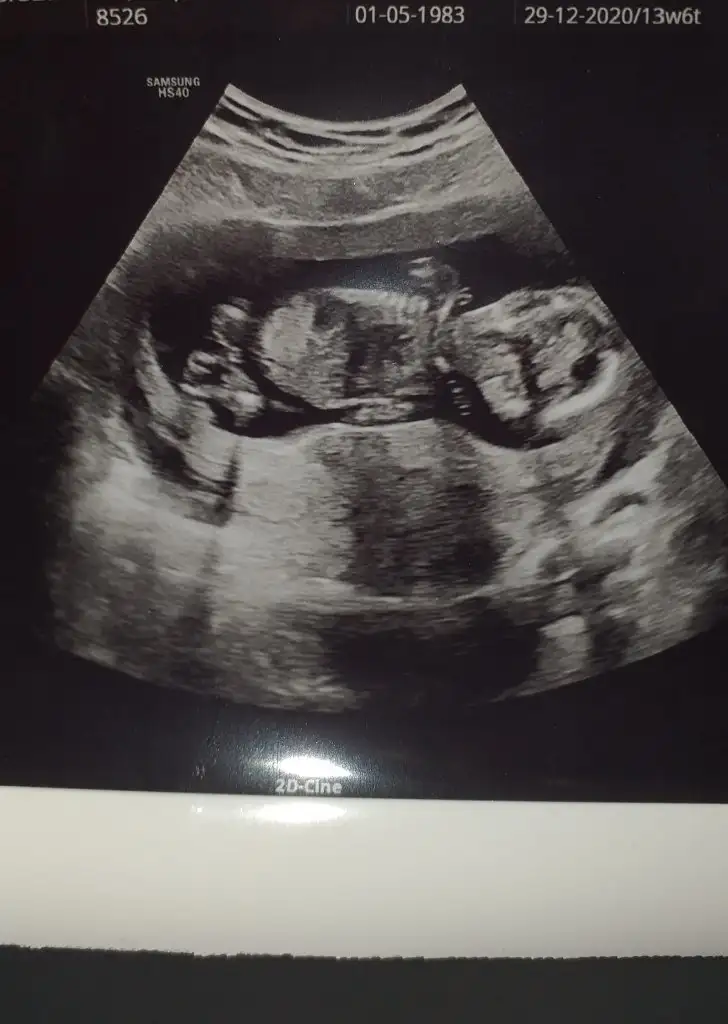

dr soylemeden siz gorun genital nub teorisi ( bebegin cinsiyeti)

En neti bu, burda 11+6lık. İlk paylaştığımda 13+3tü.

Erkek ve kız için 11 yada 12 hafta usg görüntüsü olmalı açıklamalar asagıda yazıyor 😊 rabbim herkesin gönlüne göre nasip etsin inşallah .. ecmain

[/B]Eki Görüntüle 473828 gordugunuz gibi ust taraftaki simgedende anlasildigi gibi eger cikinti paralel ise kiz

yok 30°lik bir aciyla yukari dogru bakiyorsa %99 oglunuz olacak demektir simdi bi kac ornek resimler daha koyacagim kiziminkide dahil

Eki Görüntüle 473829 bu bir erkek bebek genital nub cikintisi gayet yukarda

Eki Görüntüle 473831 simdi burada cikintilara bakin eger bel popo cizgisine paralel ise kiz

yok 30 derecelik bir aciyla yukari bakiyorsa erkek

yabancilarin hepsi biliyor bunu biz neden eksik kalalim gayet bilimsel simdi ellerinde11 12 13 ultrason fotografi olanlar alsin hemen baksin yada koyalim buraya yorumlayalim

iste o nub teorisi kizlar dr buradan yola cikiyor

Kızlar bana da tahminde bulunur musunuz doktor erkeğe benziyor dedi ama benim hala umudum var belki kız olur diye 🥰